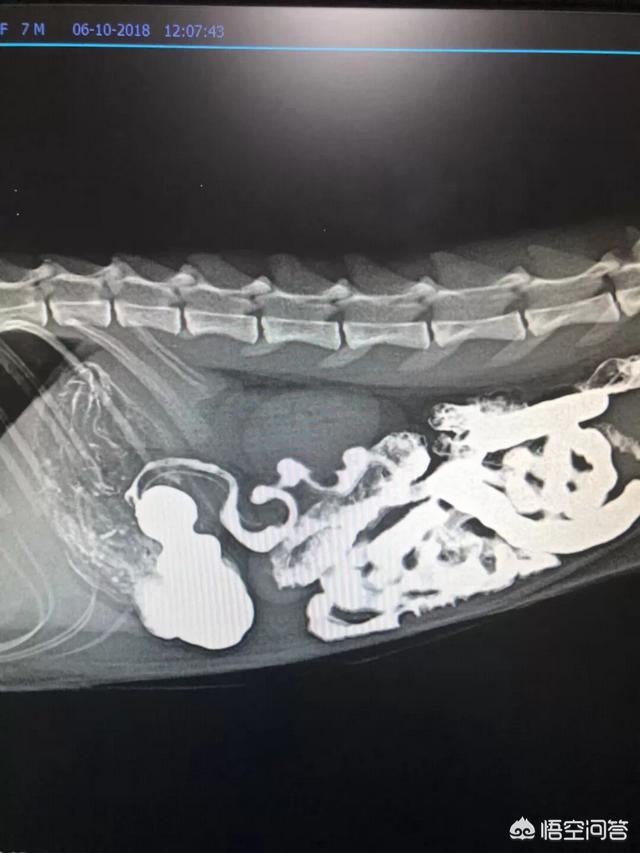

第一,猫咪绝育没有绝育之前,发情期间会出去造成咬伤甚至出现败血症等,在外部受到其他猎物追击或者挨饿受冻的的概率会急剧会增加。大家都会知道发情期间的猫咪,不管是公猫还是母的猫咪有可能就特别喜欢外出,在外面以后,可能遇到各种各样的问题。第二,猫咪做完绝育之后。对于母猫来说子宫蓄脓和乳腺肿瘤的发病率会低很多。对于子宫蓄脓,大家可能都比较熟悉,这主要是因为激素原因造成的。对于乳腺肿瘤,特别是猫咪乳腺肿瘤百分之九十以上都是属于恶性的,所以这一块需要特别的注意。

猫咪频繁发情会造成生殖系统疾病,母猫会发生卵巢、子宫和乳房病变,公猫则容易产生生殖器和尿路问题。